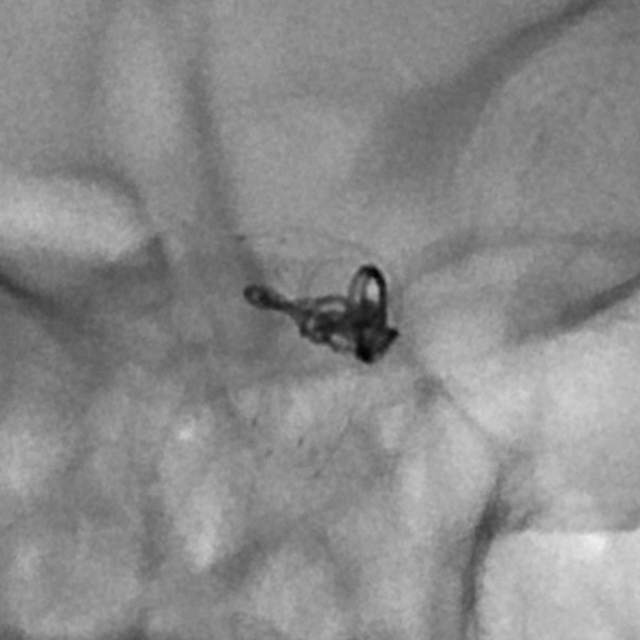

病情变化:中年男性患者,由于头晕查体发现后交通动脉瘤,第一次造影可见形态尚规则,患者及家属经过反反复复的思想斗争,决定采用外科干预。3天后,术中发现动脉瘤的形态已经出现改变,瘤囊的远端出现子瘤。